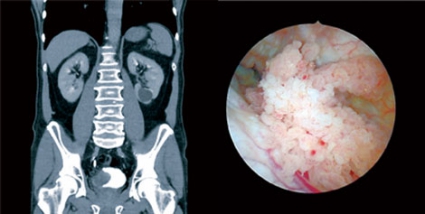

Xamirturush infektsiyasi bolgan vaginaning fotosurati